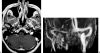

The anatomy of the jugular foramen is complex. It contains the lower cranial nerves and major vascular structures. Tumors that develop within it, or extend into it, provide significant diagnostic and surgical challenges. In this article, we describe the anatomy of the jugular foramen and outline an imaging protocol that can differentiate between lesions, thereby aiding diagnosis and facilitating management.